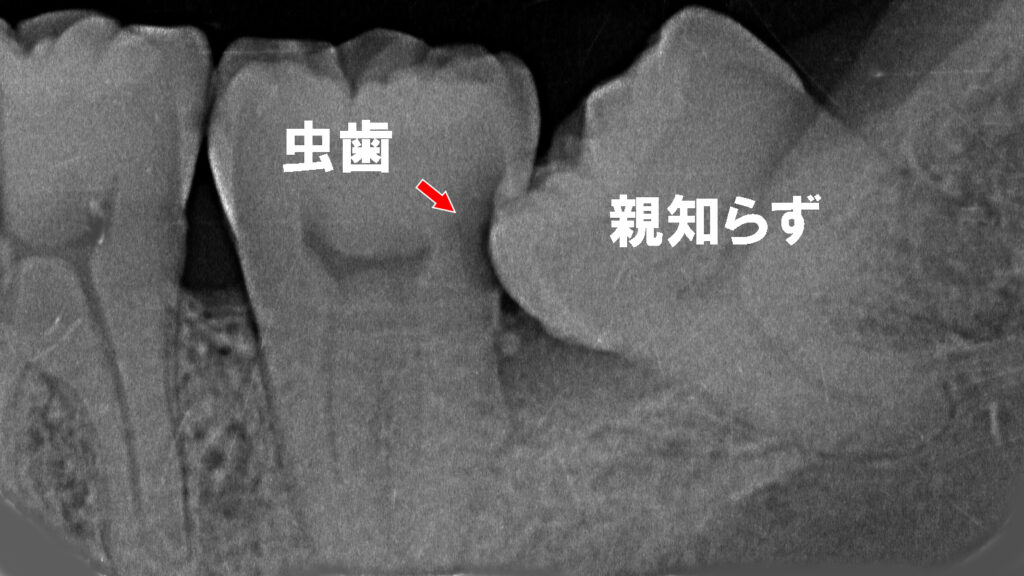

🦷① 隣の歯が虫歯になるリスクが高まる

親知らずが斜めに生えて隣の第二大臼歯(金属冠の歯)に接触すると、その間に歯垢や食べかすが溜まりやすくなり、両方の歯が虫歯になる可能性が高くなります。特に金属冠の下は虫歯の進行に気づきにくく、気づいた時には大きく進行していることもあります。